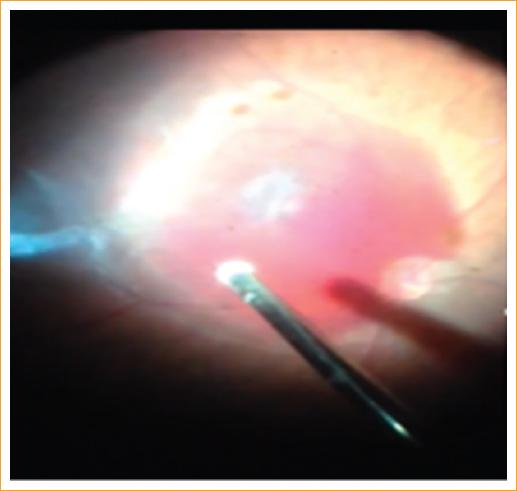

Entre los hallazgos oftalmológicos, todos los pacientes sufrieron lesiones intraoculares bilaterales: el 100% presentaron hemorragias intrarretinianas en uno o ambos ojos, el 36% presentaron hemorragia subhialoidea, el 21% presentaron hemorragia vítrea de grado IV y el 21% presentaron agujero macular postraumático (Tabla 5, Fig. 5). El 29% de los pacientes requirió cirugía de vitrectomía vía pars plana por hemorragia vítrea persistente y agujero macular traumático (Fig. 6).

En la presente serie de casos, el 86% de los pacientes presentaron crisis convulsivas, lo que fue muy sugestivo de encefalopatía, el 100% presentaron hemorragias intrarretinianas y, entre otros hallazgos, fracturas tibiales, costales, acromiales, craneales, hematomas y mordidas. Todos estos hallazgos en los pacientes nos hicieron sospechar un síndrome del niño maltratado.